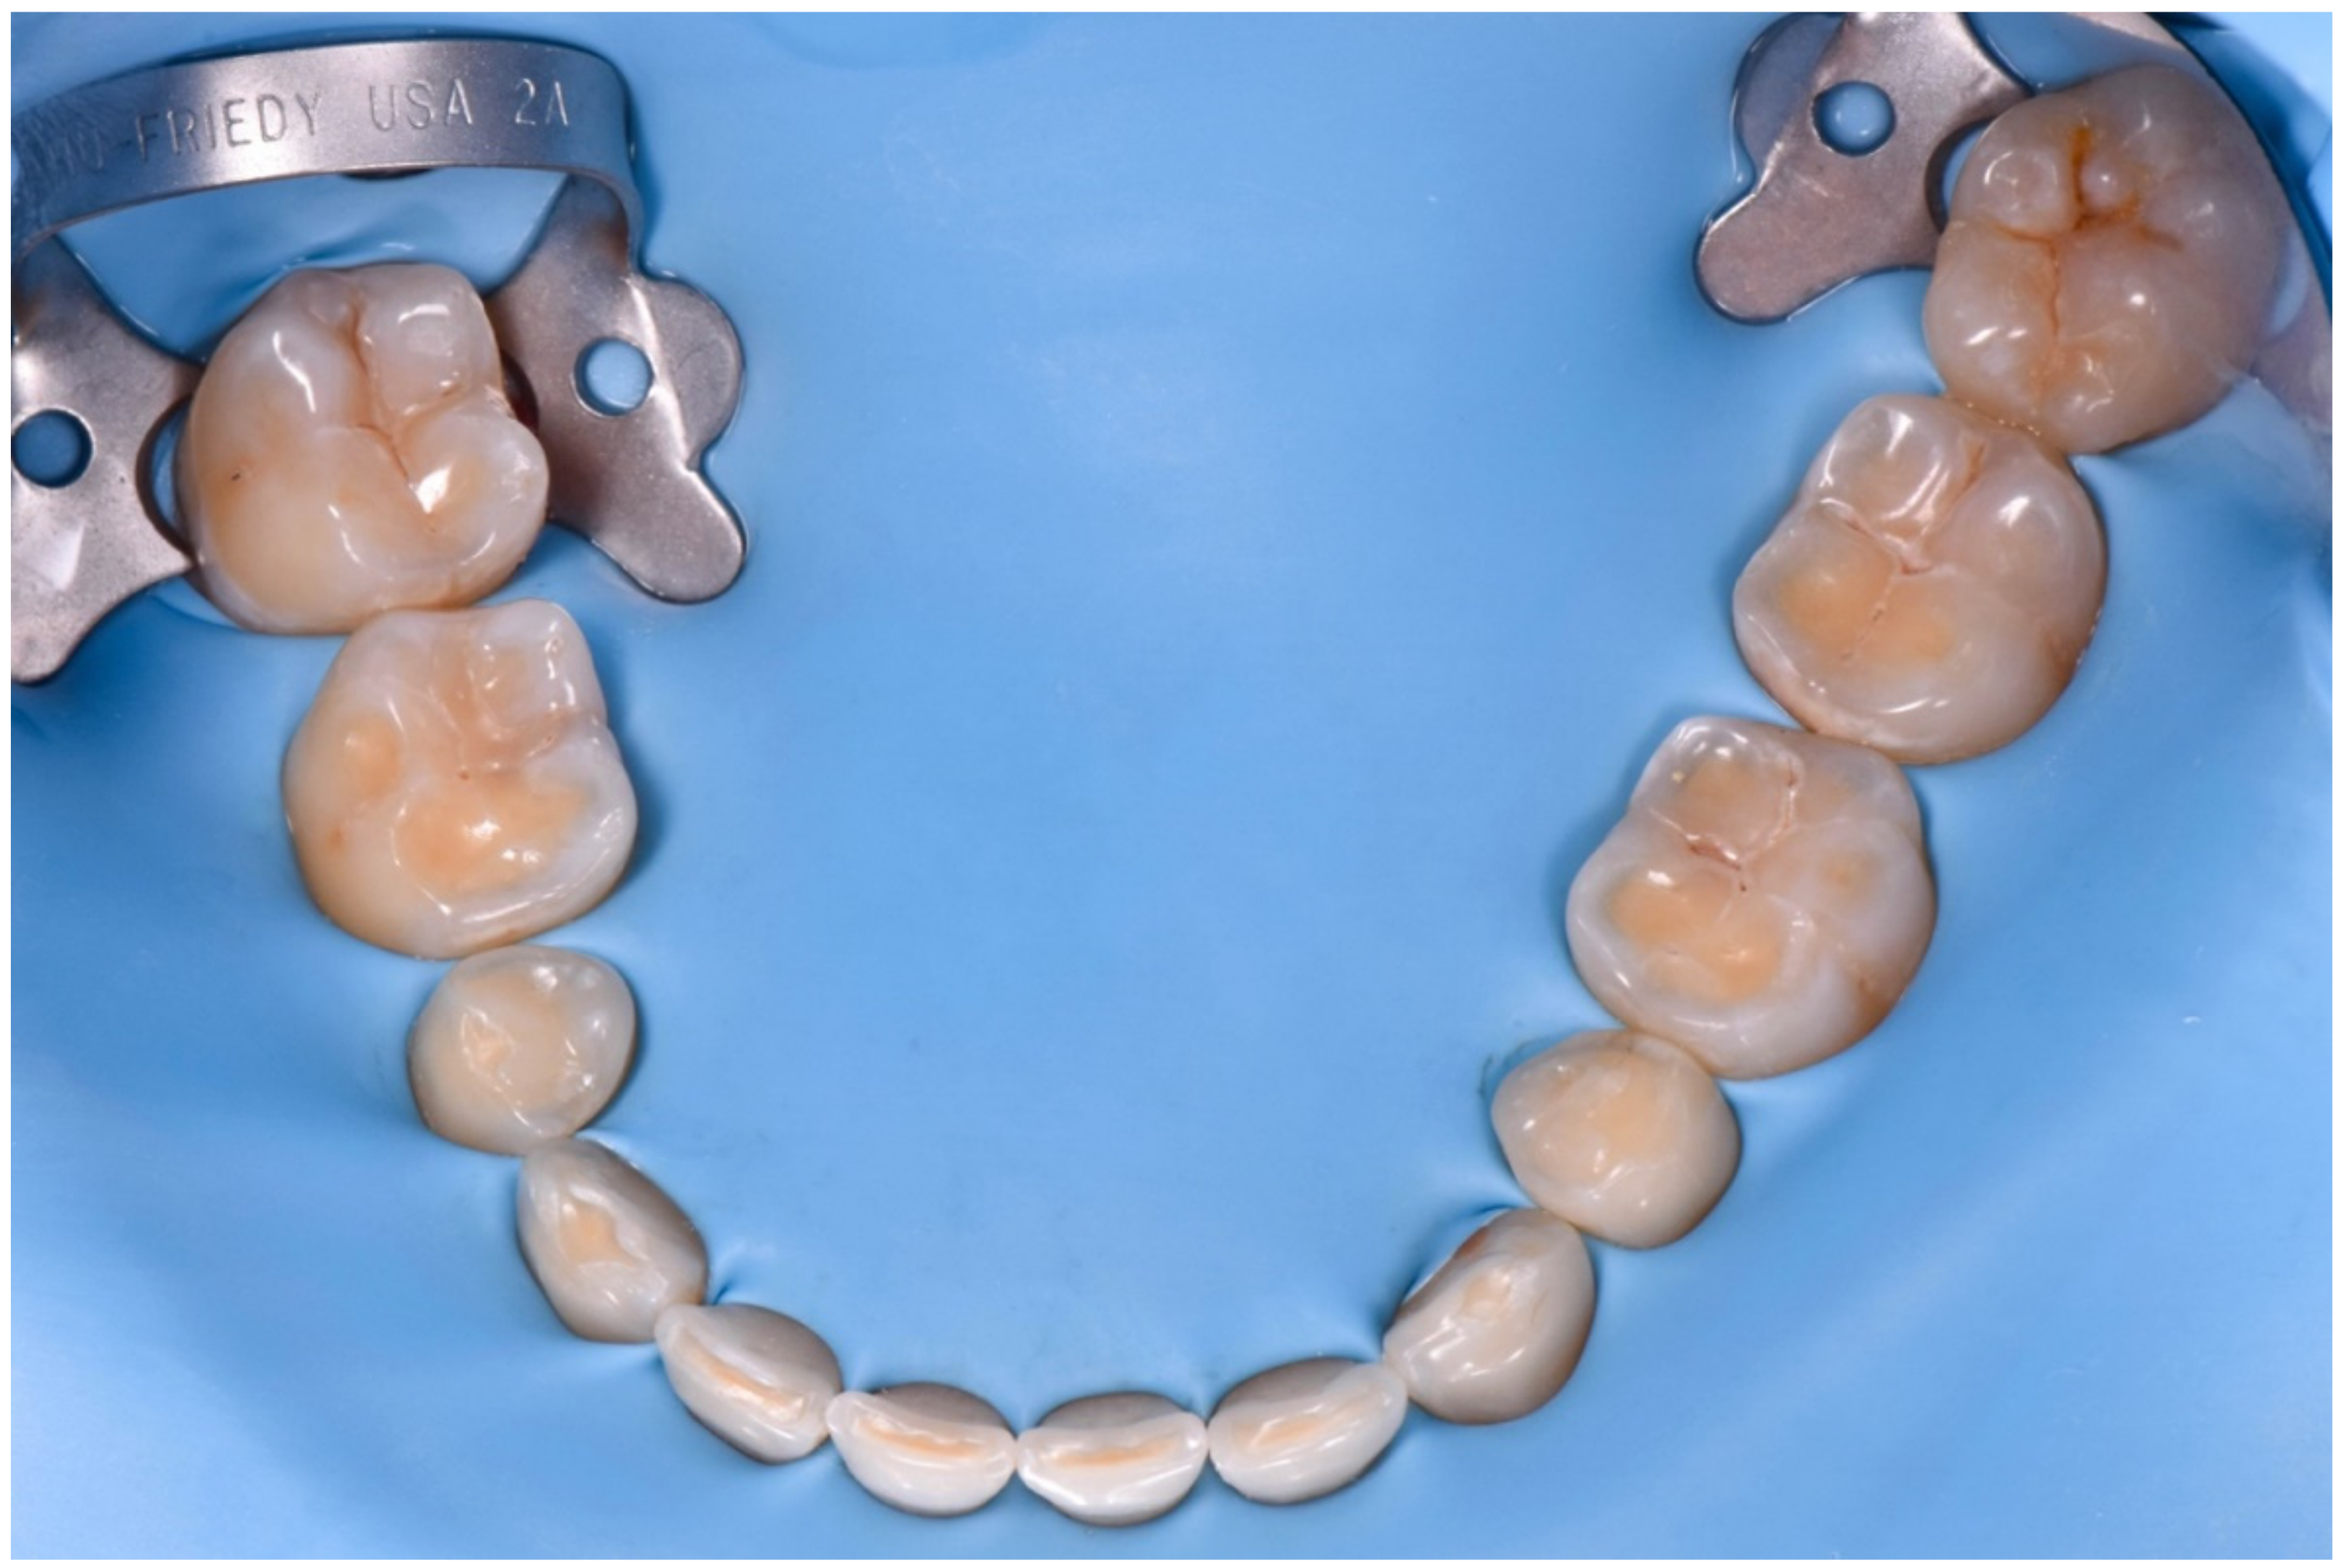

2.2. Restorative Phase